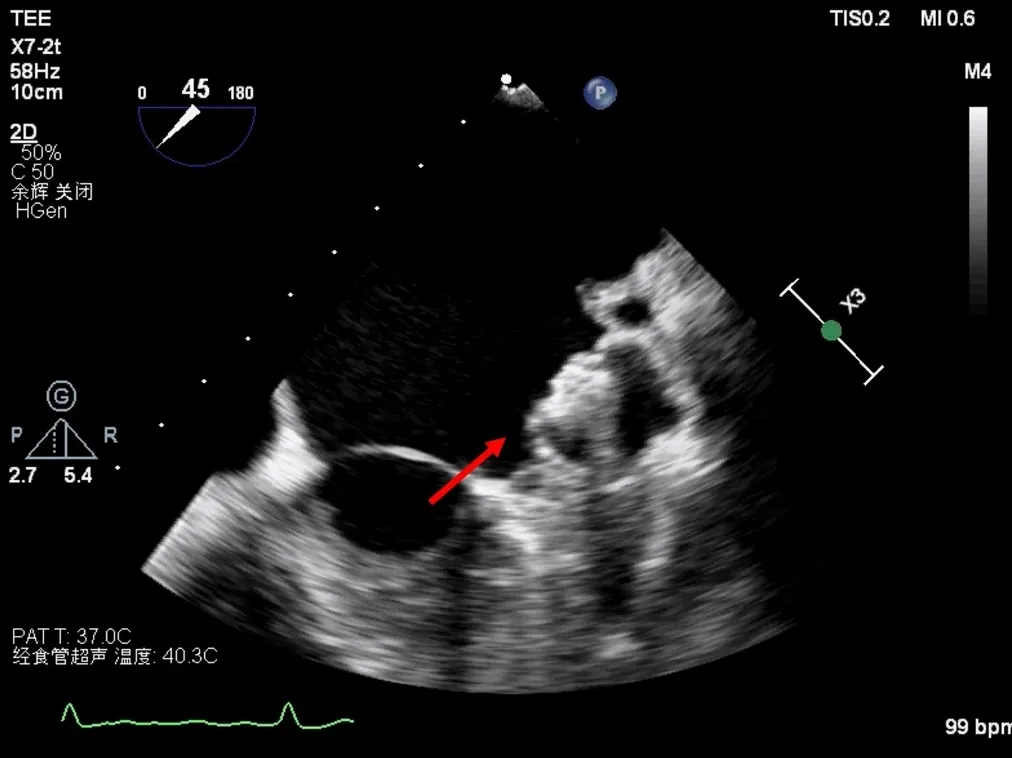

选择27mm Watchman FLX(Boston Scientific)左心耳封堵器,置入顺利,位置良好,压缩比合适,无残余漏,牵拉试验稳定。完成后交换输送鞘,选择D‐Shufo(Vickor)卵圆孔封堵器(30mm),完全覆盖ASA与PFO,TEE无残余分流。

植入后左心耳封堵器(TEE)

置入后PFO封堵器(TEE)